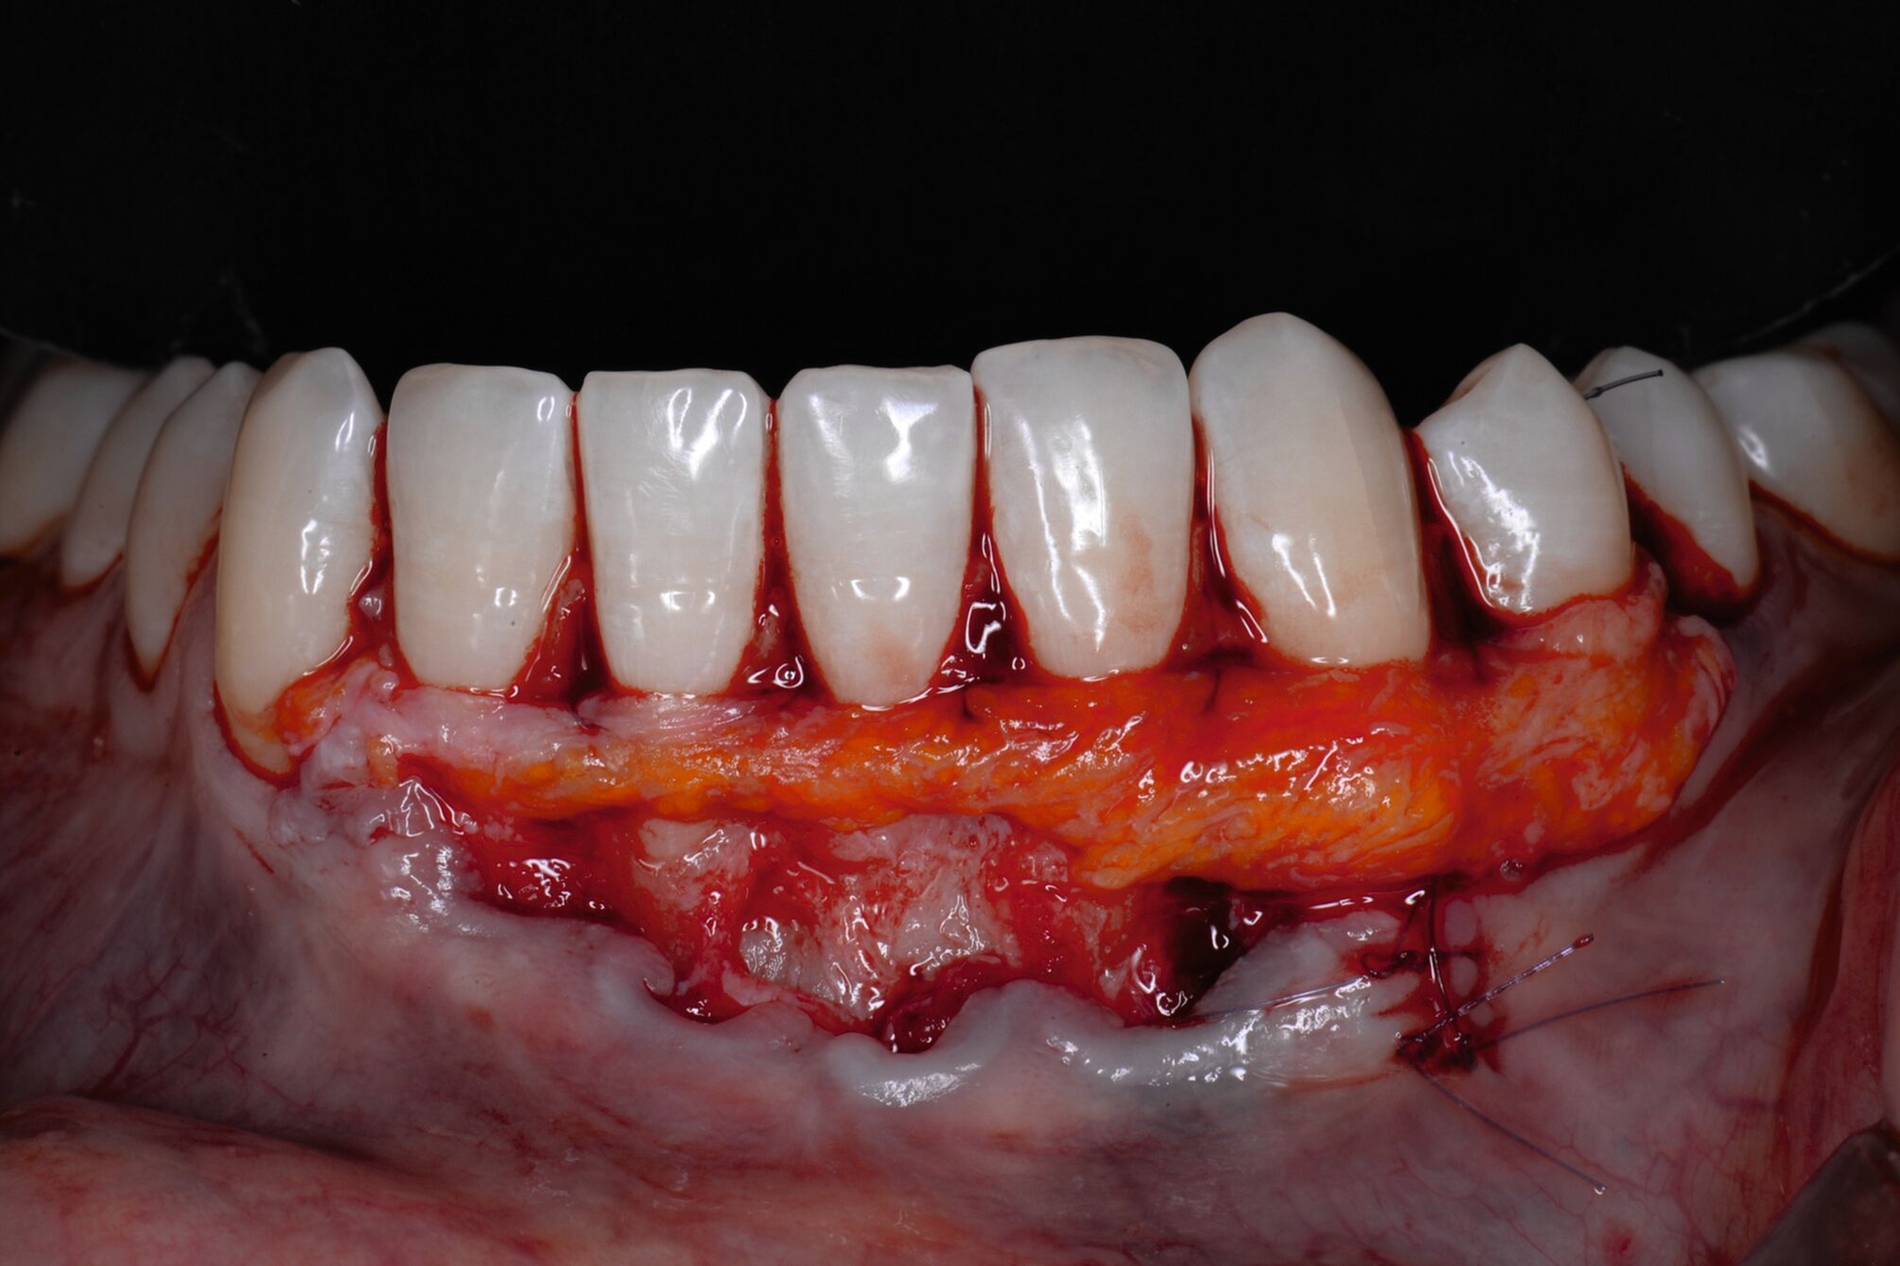

Die Papillenbereiche werden mit dem Skalpell scharf vom Periost abgelöst. Dann wird das Periost durchtrennt und bis zur mukogingivalen Grenze ein vollschichtiger Lappen gebildet. Nach Überschreiten dieser wird wieder zweischichtig präpariert. Hierdurch wird eine gute Mobilisation des Lappens erreicht, die eine ausreichende Koronalverschiebung ermöglicht. Entgegen dem in früheren Jahren propagierten komplett teilschichtigen Vorgehen, kann durch dieses Verfahren die Gefahr von Lappenperforationen signifikant gesenkt werden, da diese insbesondere im Bereich der mukogingivalen Grenze auftreten. Nachdem die Lappenareale mesial und distal der Rezession gelöst sind, können diese durch zwei bis drei feine monofile Nähte miteinander verbunden werden (Abbildung 3c). Sobald durch diese Naht ein zusammenhängender koronaler Verschiebelappen entstanden ist, werden die Papillenbereiche koronal des gebildeten Lappens entepithelialisiert. Nach Entnahme eines Bindegewebstransplantats oder entepithelialisierten freien Schleimhauttransplantats wird die Wurzeloberfläche mit EDTA-Gel konditioniert und anschließend werden Schmelz-Matrix-Proteine aufgetragen (Abbildung 3d). Diese bewirken die Bildung eines new attachment und fördern zudem die Wundheilung, was gerade bei den delikaten lateralen Verschiebelappen von Vorteil sein sollte [McGuire und Cochran, 2003; Almqvist et al., 2011; Thoma et al., 2011; McGuire et al., 2016]. Anschließend wird das Transplantat durch Nähte ausgehend vom oralen Papillenbereich fixiert (Abbildung 3e). Zuletzt wird der Lappen mit sogenannten doppelten Umschlingungsnähten im Bereich der Papille durch Zug nach koronal und oral fixiert, was eine perfekte Positionierung ermöglicht [Zuhr et al., 2009] (Abbildung 3f). Hierbei muss darauf geachtet werden, dass der Lappen die Schmelz-Zement-Grenze um mindestens 2 mm überdeckt, um eine hundertprozentige Wurzeldeckung erwartbar zu machen [Pini Prato et al., 2005].

Der Lateral Geschlossene Koronal Verschobene Lappen ermöglicht eine annähernd narbenfreie Deckung singulärer parodontaler Rezessionen durch Verzicht auf vertikale Entlastungsinzisionen (Abbildung 3g). Das Lösen der Papillen im Rahmen der Verschiebung ermöglicht eine deutliche Anhebung des Lappens und somit durch großzügige Überdeckung das Erreichen vollständiger Wurzeldeckungen. Durch den lateralen Verschluss im Rahmen der tiefen, über die mukogingivale Grenze hinausgehenden Rezession kann keratinisierte Gingiva im Bereich dieser hergestellt und eine übermäßige Mobilisation und damit Einschränkung des Vestibulums verhindert werden.

Jetzt wird beginnend an einer Seite der erste Lappenanteil nach dem Prinzip teilschichtig-vollschichtig-teilschichtig gelöst und im Bereich der ersten tiefen Rezession mittels feiner monofiler Nähte mit dem proximalen Lappenanteil vernäht. Dieser wird daraufhin gelöst und bei der nächsten tiefen Rezession erneut mit dem nahe gelegenen Lappenanteil verbunden. Dieser Vorgang wird fortgeführt, bis so erneut ein großer gesamter Lappen entstanden ist, der koronal verschoben werden kann (Abbildung 4c). Das weitere Vorgehen ist exakt wie bei der LCAF-Technik: Entepithelialisierung der Papillenareale, Gewinnung des Transplantats, Applikation von EDTA-Gel und Schmelz-Matrix-Proteinen, Fixation des Transplantats und Fixierung des Lappens nach koronal (Abbildungen 4d bis 4f). Die runden Entlastungsinzisionen lassen sich meist ohne größere Mühe verschließen, selbst wenn multiple tiefe Rezessionen vernäht worden sind.